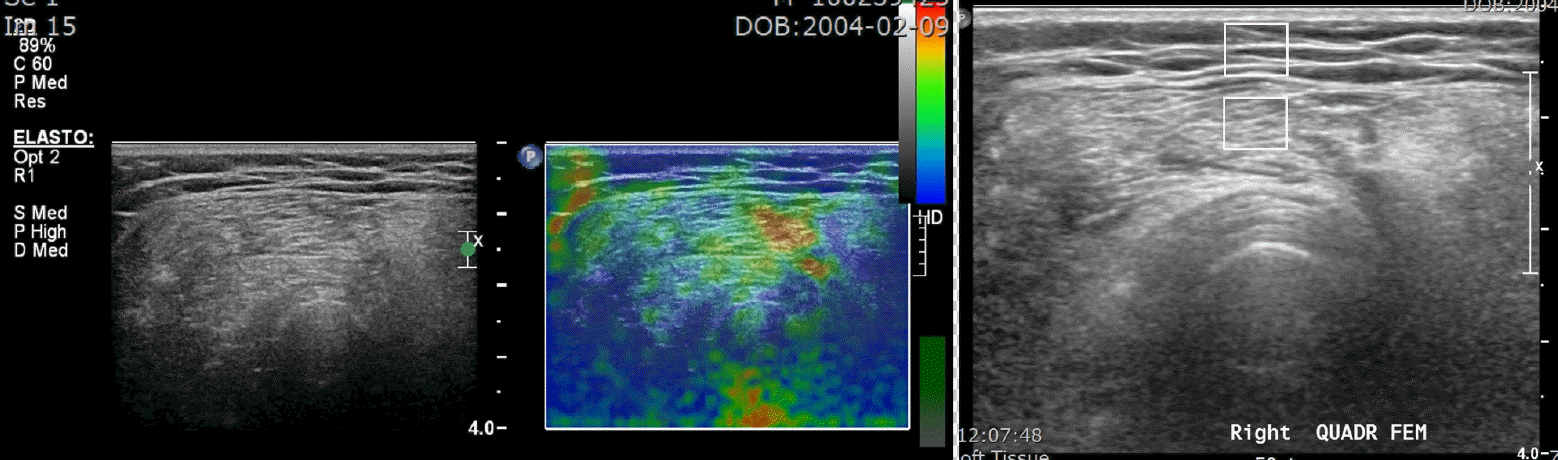

16. Kwon DR, Park GY, Lee SU, Chung I. Spastic cerebral palsy in children: dynamic sonoelastographic findings of medial gastrocnemius. Radiology. 2012; 263:794–801.

17. Kim JN, Park HJ, Kim MS, Won SY, Song E, Kim M, et al. The reproducibility of shear wave and strain elastography in epidermal cysts. Ultrasonography. 2022; 41:698–705.

18. Chang KV, Wu WT, Chen IJ, Lin CY. Strain ratio of ultrasound elastography for the evaluation of tendon elasticity. Korean J Radiol. 2020; 21:384–5.

19. Aşkın A, Kalaycı ÖT, Bayram KB, Tosun A, Demirdal ÜS, Atar E, et al. Strain sonoelastographic evaluation of biceps muscle intrinsic stiffness after botulinum toxin-A injection. Top Stroke Rehabil. 2017; 24:12–7.

21. Brandenburg JE, Eby SF, Song P, Zhao H, Brault JS, Chen S, et al. Ultrasound elastography: the new frontier in direct measurement of muscle stiffness. Arch Phys Med Rehabil. 2014; 95:2207–19.